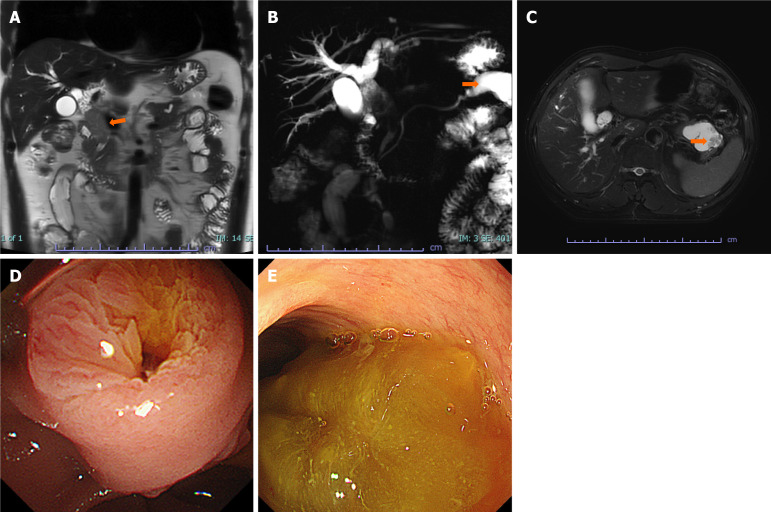

Case summary: A 58-year-old Chinese man presented with recurrent upper abdominal pain. Imaging and laboratory tests revealed lesions consistent with IPNB and IPMN. Postoperative pathological examination confirmed IPNB with high-grade dysplasia and main-duct type IPMN with low-grade dysplasia. The patient underwent extrahepatic bile duct resection with Roux-en-Y choledochoenterostomy and distal pancreatectomy. He had an excellent prognosis with no tumor recurrence during the 30-month follow-up.